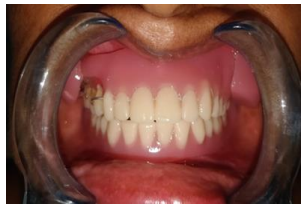

A 49 years old female patient reported to the department of prosthodontics with multiple missing teeth and sunken cheeks. Intra oral examination revealed that the mandibular was completely edentulous and the maxillary arch had three upper right posterior teeth. The patient had moderately resorbed maxillary and severely resorbed mandibular edentulous ridges. The patient was conscious about her sunken cheeks and desired a prosthesis that would make her face look fuller and healthier.

Treatment plan was formulated, keeping the patient’s demand in mind. It was decided to give the patient mandibular complete denture and maxillary dentures with magnet retained cheek plumpers.

Primary impressions of maxillary and mandibular arches were made using impression material (Y Dents, MDM Corporation, Delhi). Custom trays were made using autopolymerizing acrylic resin. Border molding was done using low fusing impression compound (DPI Pinnacle, The Bombay Burmah Trading Corporation Limited, Mumbai, India) and wash impression was made with medium body addition silicone impression material (Aquasil, Dentsply). Jaw relations were recorded. For the try-in appointment waxed denture was first tried for occlusion and esthetics. At the same appointment, cheek plumpers were made in wax and were attached to the upper waxed-up denture. Then it was evaluated to give the patient a fuller appearance. A dramatic change in the appearance with and without wax-up cheek plumper was observed and it was immediately accepted by the patient. The waxed plumper was separated from the waxed-up denture. After that flasking and dewaxing procedures were completed separately for the final prosthesis and cheek plumpers. The mold space was packed with heat-polymerizing acrylic material (DPI, Mumbai, India) and curing procedures were performed according to the manufacturer’s instructions. After deflasking, the cured final prosthesis and plumpers were retrieved. Trimming, finishing, and polishing procedures were performed. Then a pair of commercially available magnets (cobaltsamarium, Ambika Corporation, New Delhi, India), 5 mm in diameter and 2 mm in thickness was employed to retain the cheek plumper with final prosthesis. Provision for placement of magnets in the flange of the final prosthesis and in the cheek plumper was made and positioned with the help of autopolymerizing resin. Complete polymerization was ensured by placing in a pressure pot and finishing and polishing was then carried out. The attachment of plumper to the prosthesis was first checked outside the patient’s mouth. The prosthesis along with the plumper was then checked in the patient’s mouth. for comfort, function and esthetics . The patient was educated about the positioning of the plumper to the prosthesis. The patient’s demands were fulfilled.  She was called form follow up to evaluate any soreness or looseness of dentures.